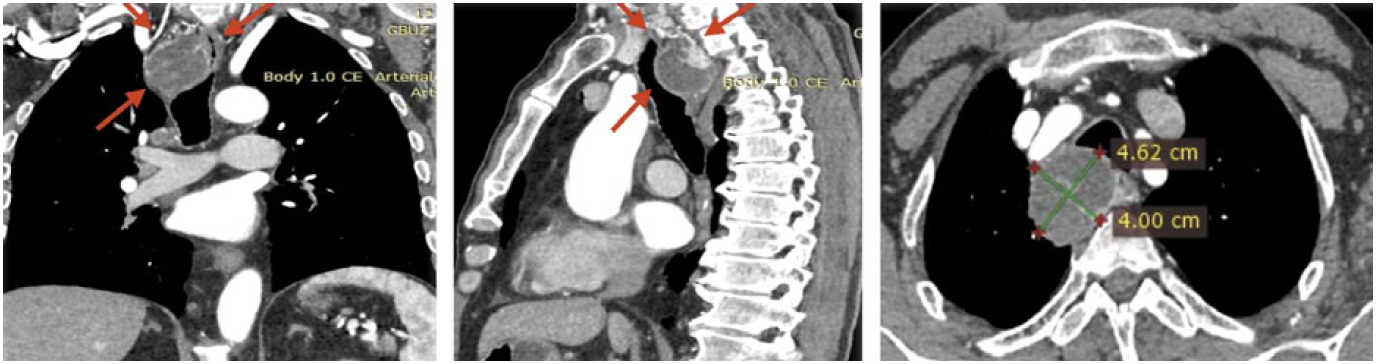

При мультиспиральной КТ с болюсным усилением по нижнему краю правой доли щитовидной железы в заднем верхнем средостении визуализируется кистозно-солидное объемное образование с четкими ровными контурами размером 46×38×48 мм, прилежит и деформирует заднюю стенку трахеи и правую боковую стенку пищевода. Солидный компонент накапливает контрастное вещество аналогично ткани щитовидной железы, определяются тонкие перегородки, накапливающие контрастное вещество. Окружающая клетчатка уплотнена (рис. 3).

Рис. 3. Результат КТ с болюсным контрастированием.

Fig. 3. The result of contrast-enhancement CT.